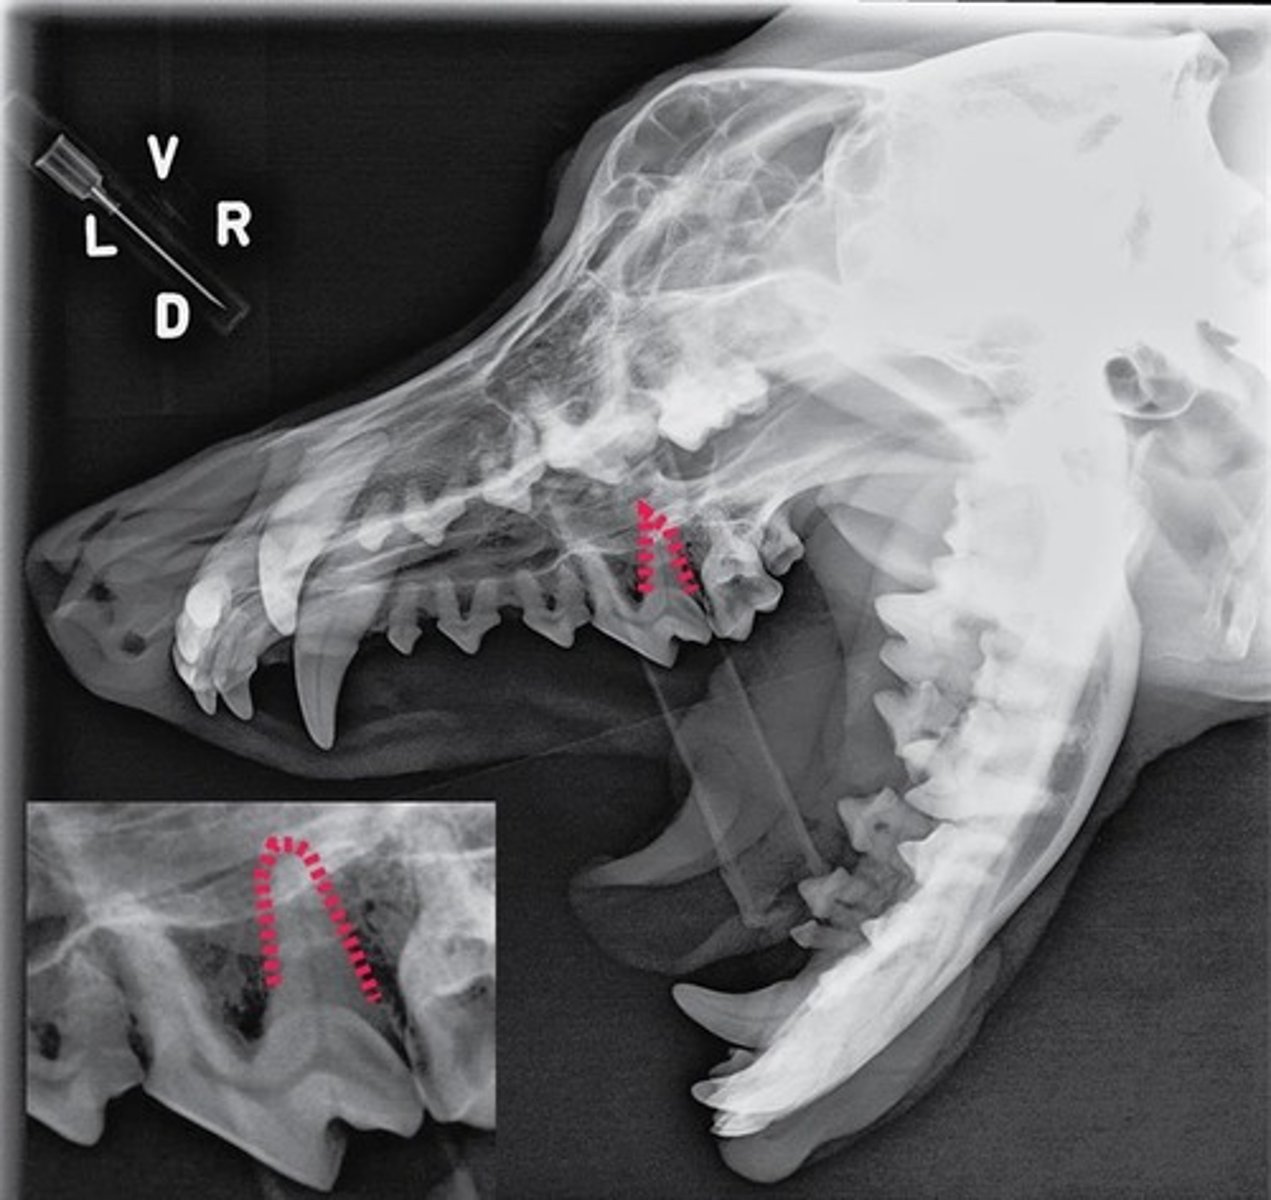

Identify the type of tooth indicated by the arrow.

Molar

Identify the type of tooth indicated by the arrow.

vestibular, buccal, facial surface

Identify the tooth surface the red line being pointed to by an arrow represents

lingual surface

Identify the tooth surface the red line being pointed to by an arrow represents

mesial surface

On the first molar, identify the surface the red line being pointed to by an arrow represents.

distal surface

On the first molar, identify the surface the red line being pointed to by an arrow represents